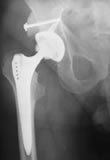

Bei einer fortgeschrittenen Arthrose des Hüftgelenks ist die Implantation einer "künstlichen Hüfte" - bestehend aus Spezialkunststoffpfanne und Titanhüftkopf - die Methode der Wahl. In der Regel wird diese zementfrei eingebracht.

Die Haltbarkeit einer künstlichen Hüfte ist von verschiedenen Faktoren, auch vom Körpergewicht, abhängig. 10 Jahre nach "Einbau" sind jedoch praktisch alle zementfrei eingebrachten Implantate noch voll funktionsfähig. Viele Hüften halten 15 - 20 Jahre. Manche auch noch länger.

In Ausnahmefällen (bei sehr betagten Patienten, die nach der Operation auf sofortige Vollbelastung angewiesen sind) verwenden wir den Geradschaft nach Maurice E. Müller - ein zementierten Hüftschaft, der bereits über 1 Million mal weltweit implantiert wurde, und auch eine sehr lange Haltbarkeit aufweist.